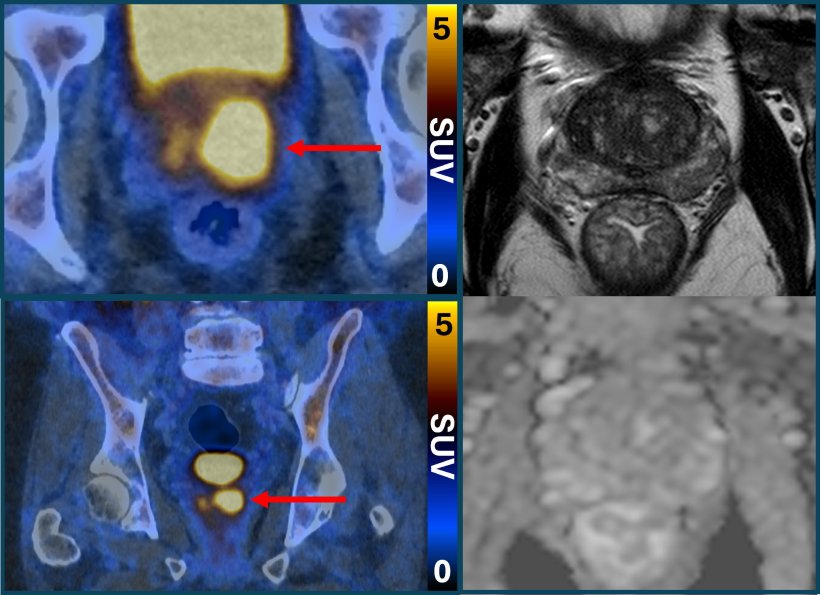

The PSMA PET/CT scan identifies more aggressive prostate cancer cells, which are potentially harmful and may need treatment. It does this with a molecule that binds to prostate cancer cells and causes them to ‘glow’, appearing as bright spots in the scanning image. This could also help reduce the risk of overdiagnosis by determining which cancers are low-risk and will never cause harm, the study says.

PSMA PET/CT scanning makes prostate cancer cells light up in a remarkable way, particularly in more aggressive cancers

Dr James Buteau, a nuclear medicine physician at Peter MacCallum Cancer Centre, is presenting the research at EAU26. He said: “PSMA PET/CT scanning makes prostate cancer cells light up in a remarkable way, particularly in more aggressive cancers. It’s rare to see such strong imaging that could be so powerful in the clinic. Incorporating this testing into clinical care could help to address the major challenge of prostate cancer overdiagnosis, which leads to at best unnecessary and at worst harmful treatment for cancers that would never cause any harm.”